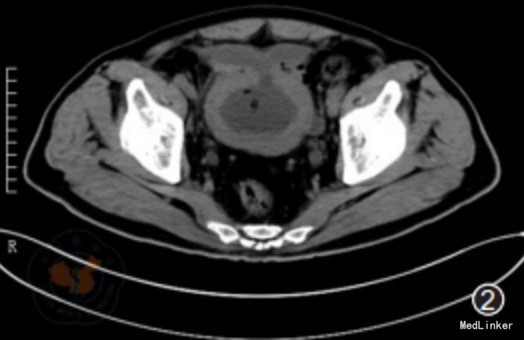

入院后予以留置导尿,硬膜外麻醉下行经尿道前列腺等离子电切术(transurethralplasma kinetic prostatectomy,TUPKP)。术中见前列腺中叶、两侧叶均明显增生,突向膀胱内呈球形,距精阜约4个视野。电切过程中用Ellik冲洗器冲出组织碎片。当电切膀胱颈顶部时闻及爆炸声,立即怀疑膀胱内气体爆炸并停止电切。镜下检视膀胱发现前壁有一直径约25px破裂口。因患者一般情况良好,各项生命体征平稳,无明显腹胀、腹肌紧张,故降低冲洗速度,继续修整切除前列腺尖部增生腺体。术后留置导尿、缓慢膀胱冲洗。术后CT检查显示膀胱前壁有一破裂口,位于腹膜外(图2)